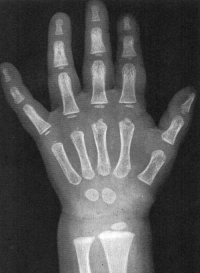

Sexo Masculino

Recém-Nascido

idade óssea - RN

Sexo Feminino

Fonte: GREULICH, W.W. & PYLE, S.I.: Radiografic Atlas of Development of the Hand and Wrist. Stanford University Press, 2° edition, 1959.